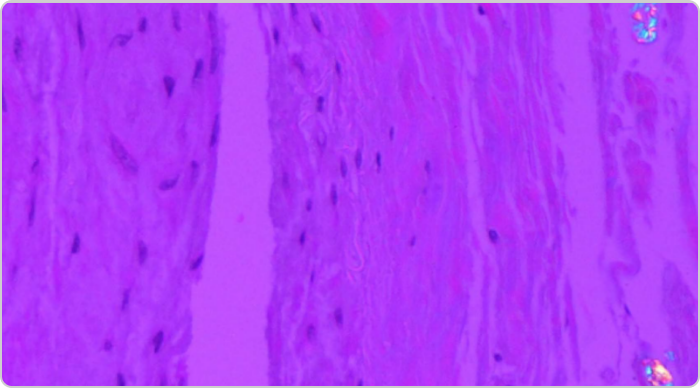

Photo of tophi from gout in spine

(A) Intraoperative photograph of the chalky white material at the right L2-L3, L4-L5 facet joints (white arrows).

(B) Histological examination (H&E, 100x) shows amorphous tophaceous deposit with a multinucleated giant cell reaction.2

Adapted from Lu H, et al. Medicine (Baltimore). 2017;96:e7670.

KRYSTEXXA has not been studied to reverse damage to the spine or any of the body's organ.